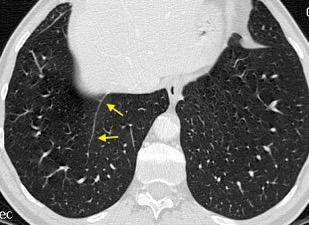

Nódulos pulmonares múltiples. (flechas verdes). Masas paratraqueales. (flechas amarillas). Dudoso ensanchamiento retrocrural (flechas negras). sigue….

Ttawfik A et al. Trans-diaphragmatic Pathologies: Anatomical Background and Spread of Disease on cross-sectional Imaging. Current Problems in Diagnostic Radiology. 2021.

T. mixto de células germinales del testículo

izquierdo Metástasis pulmonares. (flechas verdes). Ganglios paratraqueales. (flechas amarillas). Ganglios retroperitoneales (flechas negras)

Tawfik A et al. Trans-diaphragmatic Pathologies: Anatomical Background and Spread of Disease on cross-sectional Imaging. Current Problems in Diagnostic Radiology. 2021.